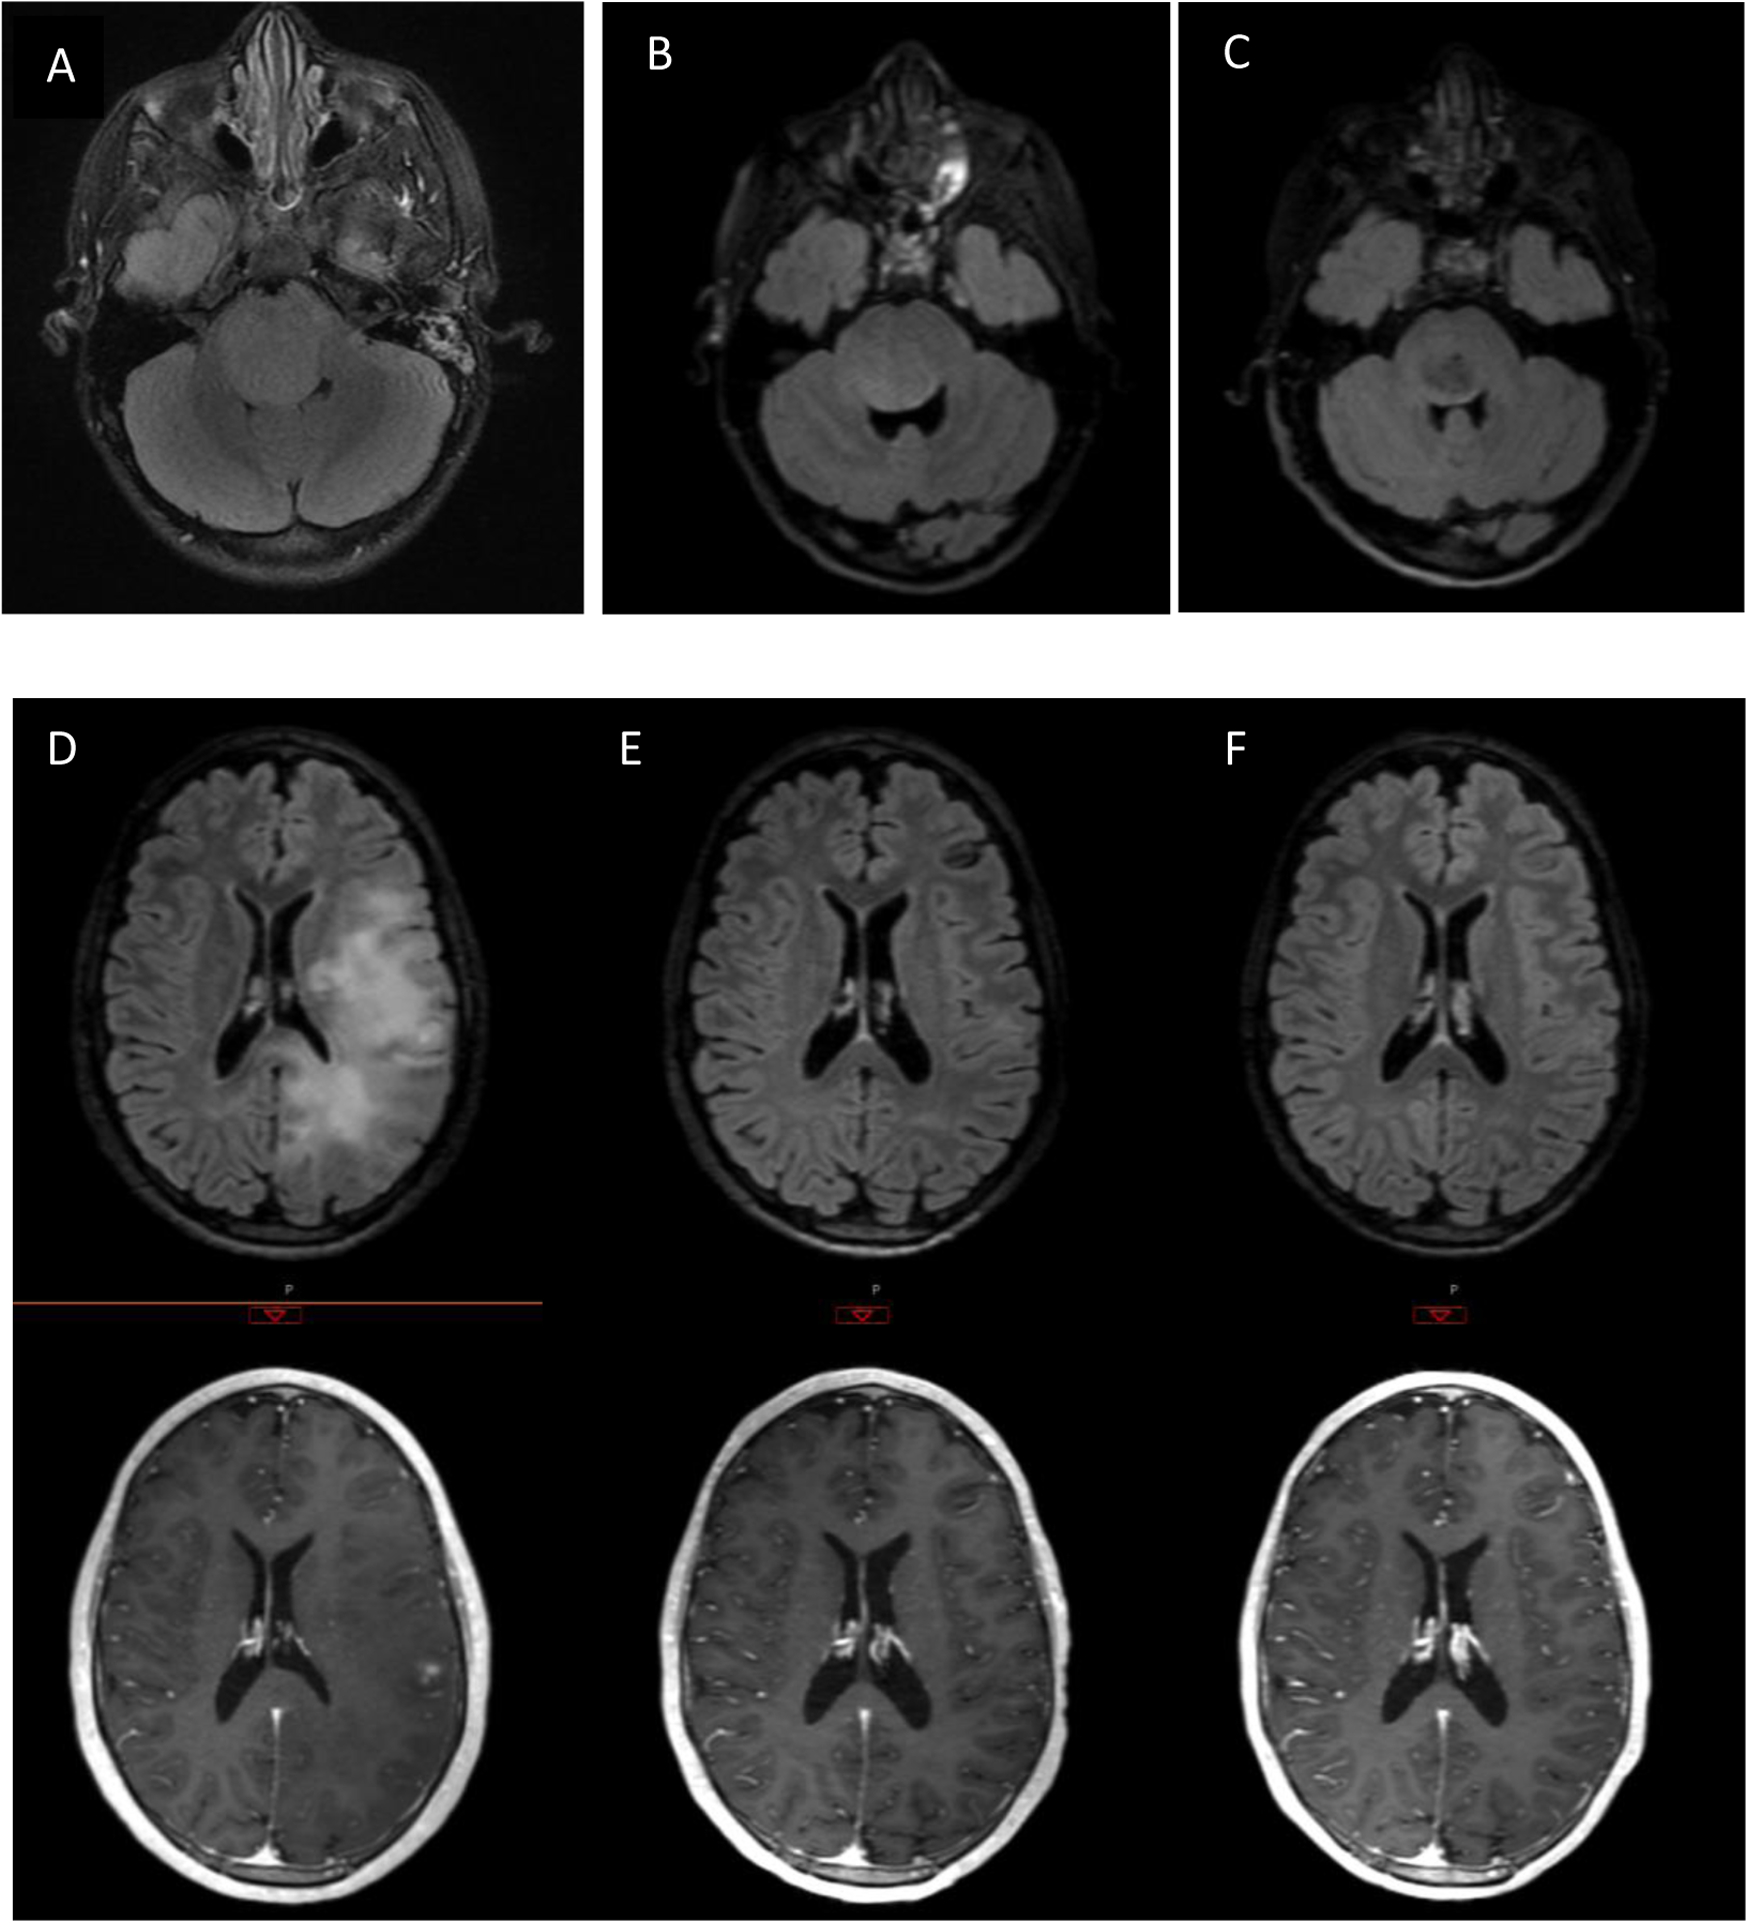

There were two exceptional responders, (Figure 1) including one patient with DIPG and one patient with HGG. The patient with DIPG was diagnosed at age 5 years, treated at dose level 116 mg/m2/d and received 55.8 Gy radiation therapy. She continued on lenalidomide maintenance therapy for 41 total cycles without any dose reductions or further interruption.

Figure 1:

Top panel: Axial FLAIR images of patient with DIPG at A) diagnosis, b) 3 months post= XRT, and c),2.5 yrs. post diagnosis. Lower panel: FLAIR and T1-post contrast axial images of patient with gliomatosis cerebri at D) diagnosis, E) post-XRT, and F) 6 mo. post-XRT

The second exceptional responder was a 19 yo male with a biopsy proven diffuse anaplastic glioma (WHO III) who enrolled on this study at dose level 88 mg/m2/d and received 54 Gy whole brain radiation therapy. He had a near complete response following radiation and lenalidomide. He required two dose reductions of lenalidomide (courses 4 and 6), but continued to have dose limiting myelosuppression. He was treated with lower dose lenalidomide off-study, but had disease recurrence 15 months after study entry.